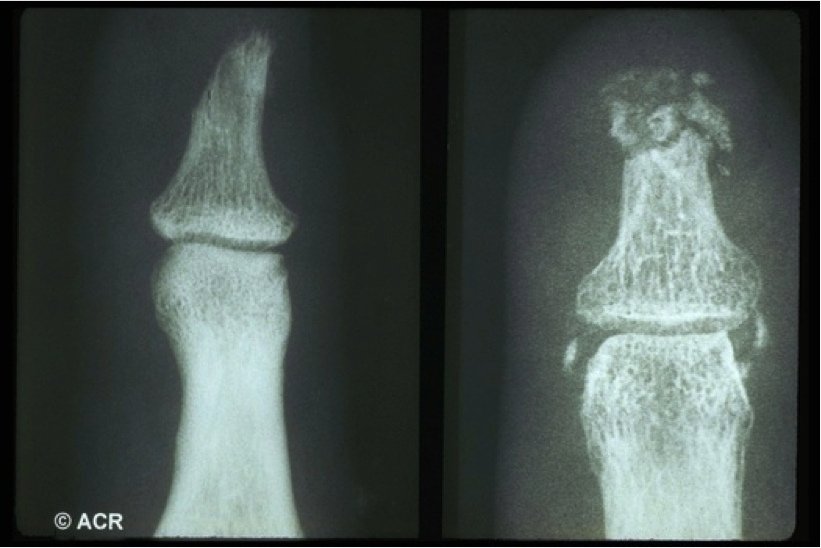

Picture of what? What disease/type?

Sclerodactyly: Systemic Sclerosis, Limited type.

Xray of sclerodactyly (below) indicates resorption of the terminal phalanges (acro-osteolysis).